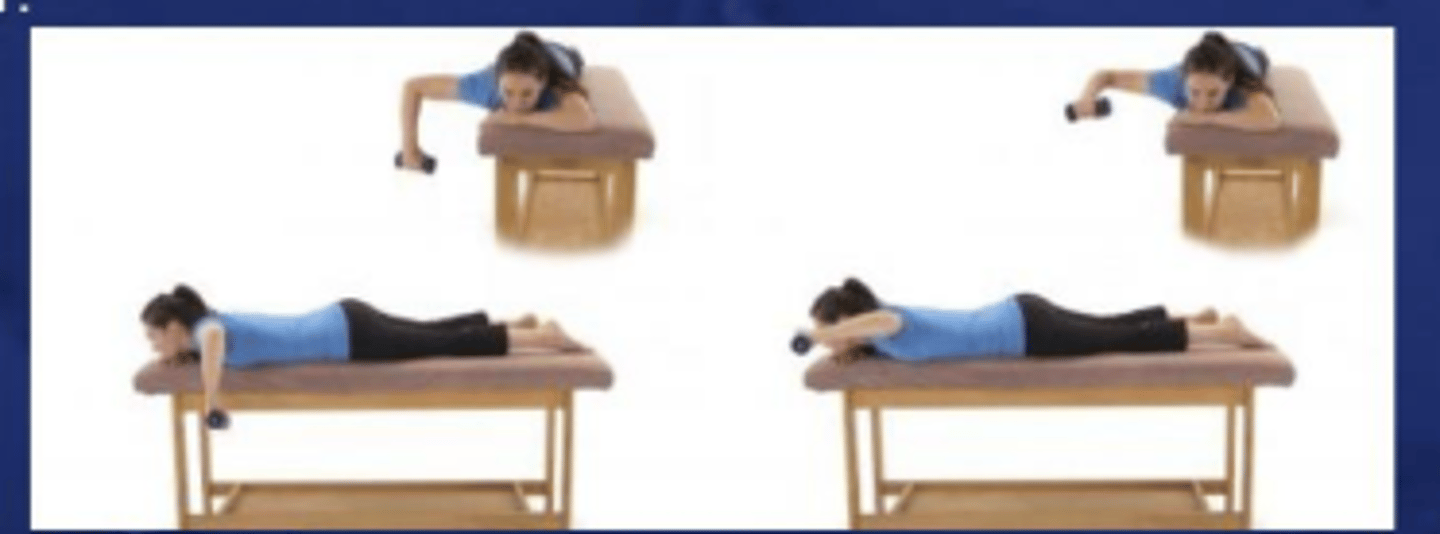

5. Prone horizontal abduction (at 120-135°)

Prone horizontal abduction to neutral

What does the image show?

Prone horizontal abduction with full ER, 100° abduction

What does the image show?

Prone rowing

What does the image show?

Prone rowing into ER

What does the image show?